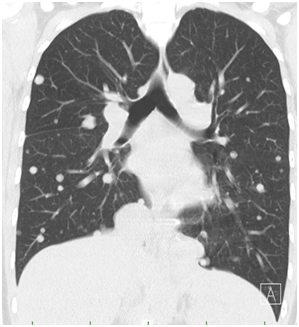

1. Static Computer Tomography (CT) scans of the chest, abdomen and small pelvis with CT biopsy sampling of the sacral expansion (Figure 1). In addition to the sacral tumorous expansion the CT scan captured suspected multiple diffuse metastatic diseases of the lungs and both pulmonary hilum (Figure 2). Other organs or the skeleton were not affected.

Figure 2 Computer Tomography scan of the multiple metastasizing processes.